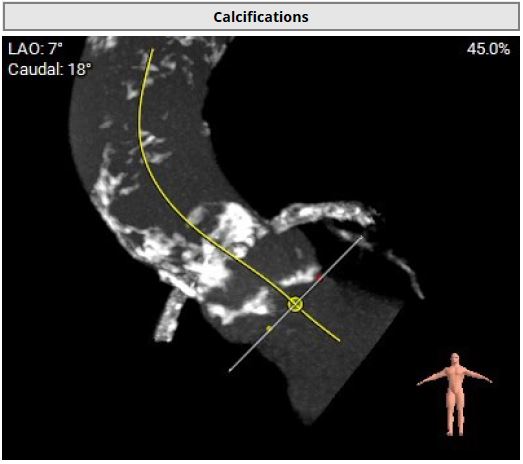

However, multislice CT scan revealed severe stenosis and calcific change in bilateral femoral arteries, making the transfemoral arterial approach unfeasible. Alternative access sites, including bilateral carotid and axillary arteries, were also not feasible. Although there was severe calcification in the abdominal aorta, the transcaval approach targeting a calcium-free segment of the aorta at the L3 level represented barely the last resort for carrying out TAVI procedures.

The transcaval approach starts with descending abdominal aortography. A 7-F renal double curve guide catheter which was advanced through the right femoral vein. An Astato wire along with a CXI microcatheter were advanced through the catheter to the indexed L3 level for transcaval puncture with the distal end of the Astato guidewire connecting with an electrosurgery pencil. After the Astato guidewire cross the vena cava and the adjacent aortic wall, the Asatato-CXI system was then captured by a 25 mm Gooseneck snare placed at the corresponding aortic level through left femoral atery, and sent upward to the thoracic aortic level. The Asatato wire was exchanged for a Lunderquist guidewire, through which an 20 French long sheath was advanced through RFV to the abdominal aorta. Standard TAVI procedures employing a Navitor 27 mm transcatheter heart valve were then performed through this vena-aortic connection facilitated by LV on-wire pacing. At the end of the procedure, an Amplatzer Duct Occluder was deployed to close the aorto-caval tract, with post-procedural angiography confirming a patent fistula with cruciform contrast flow around the neck of the occluder but with contrast returning to the cava. After careful examination, there was no extravasation on the digital subtraction angiogram. The next day, a follow-up angiogram of the aorto-caval fistula was performed, which revealed a patent fistula but without extravasation. The patient is doing well during one year of follow-up.